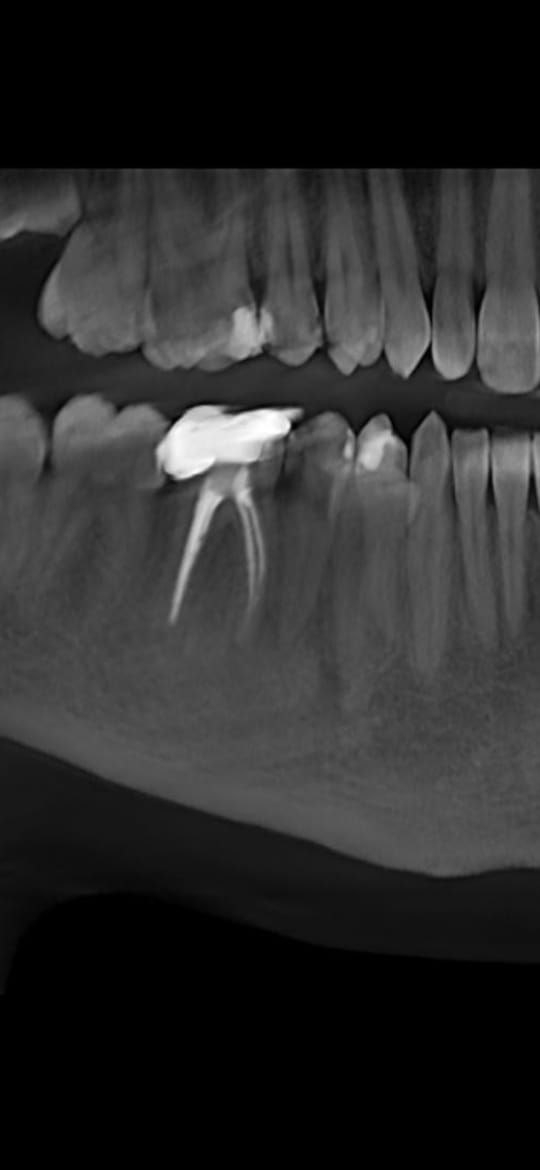

>>1656740

Забыл добавить что не болит но потерялась чувствительность, ощущение как при любом ожоге слизистой или языка

Аноним 30/01/26 Птн 14:55:19 1656772 150

345345.png 17Кб, 164x328

164x328

Вылетела пломба - ничего не болит, на жар тепло не реагирует но есть проблема. Щас на вахет, приеду 15-ого к врачу смогу попасть 16-ого. За это время ничего фатального не произойдет? Есть какие то рекомендации что делать и чего не делать что бы не усугубить до этого времени?

Аноним 30/01/26 Птн 16:01:58 1656775 151

170040858113491[...].webp 26Кб, 700x361

700x361

>>1656772

Залепи жувачькой. "Temporary Tooth Repair Kit" или "Dental Filling Material"

Аноним 30/01/26 Птн 16:11:28 1656776 152

>>1656775

Лучше такое не использовать. Сам ты нормально не очистишь зуб под выпавшей пломбой, а там скорей всего кариес минимальный есть и запечатывание может и осложнения дать за 2 недели.

Оптимально сразу обратится к врачу, но если возможности нет то аккруатная гигиена мягкой щеткой и полоскания после еды.

Аноним 31/01/26 Суб 11:11:39 1656838 153

image.png 1327Кб, 960x1280

960x1280

>>1657604

Вот даже кусок старого рентгена остался трёхлетней давности